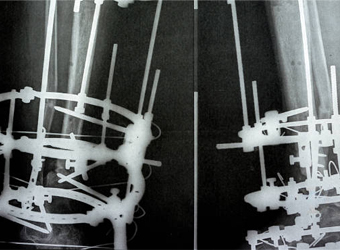

Deformity correction using the Ilizarov method is a surgical procedure that involves the use of an external fixator to realign bones and joints in the body.

Dr. Suhas Shah has been practicing as an orthopedic surgeon with super specialization in Ilizarov surgery since last 16 years. He is visiting as an Ilizarov specialist all over Maharashtra and has done more than 1400 surgeries in this specialty till now. I have been a faculty member during various Ilizarov courses & workshops held all over India.We now have a center for total Orthopedic care under one roof.

At Dr. Suhas Shah Orthopedic Center, we provide comprehensive orthopedic and trauma care under one roof, specializing in advanced techniques like Ilizarov surgery and limb lengthening & reconstruction. With over 16 years of experience, Dr. Suhas Shah has performed more than 1,400 Ilizarov surgeries and serves as a visiting Ilizarov specialist across Maharashtra.